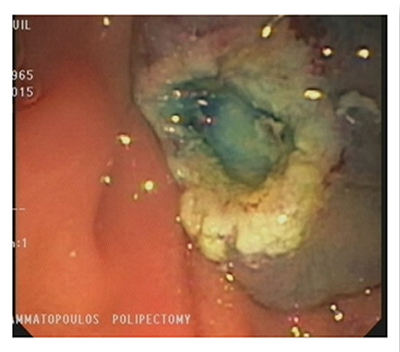

Our Hospital meets all these conditions. As a result, the endoscopic procedures are completely safe. Sessile polyps that are over 1 cm in size require special endoscopic management during polypectomy. A necessary condition is the submucosal injection of normal saline solution, with or without epinephrine, along with blue de methylene or indigo carmine. The infusion helps separate the mucosa and submucosa from the muscular layer. This technique also offers the endoscopy specialist the chance to understand whether they can remove the lesion. When the base of the polyp rises smoothly and easily, then it is possible to remove the polyp. The infusion may reduce the risk of bleeding and perforation following polypectomy.

Polyps that are over 2 cm in size may be removed in fragments or using the endoscopic submucosal dissection (ESD) method. Submucosal lesions are removed using a different procedure. Initially, the mucosa is lanced using a special lancet and the lesion is exposed. It is then separated from the surrounding tissue and removed.

Endoscopic Submucosal Dissection (ESD)

This technique was first developed in Japan for the removal of an entire large polyp in one piece during one session.

- The anatomic pathology material (one single piece sent to histology)

- Lower risk of recurrence compared to a fragmented polypectomy

Disadvantages:

- Higher risk of bleeding

- Higher risk of perforation